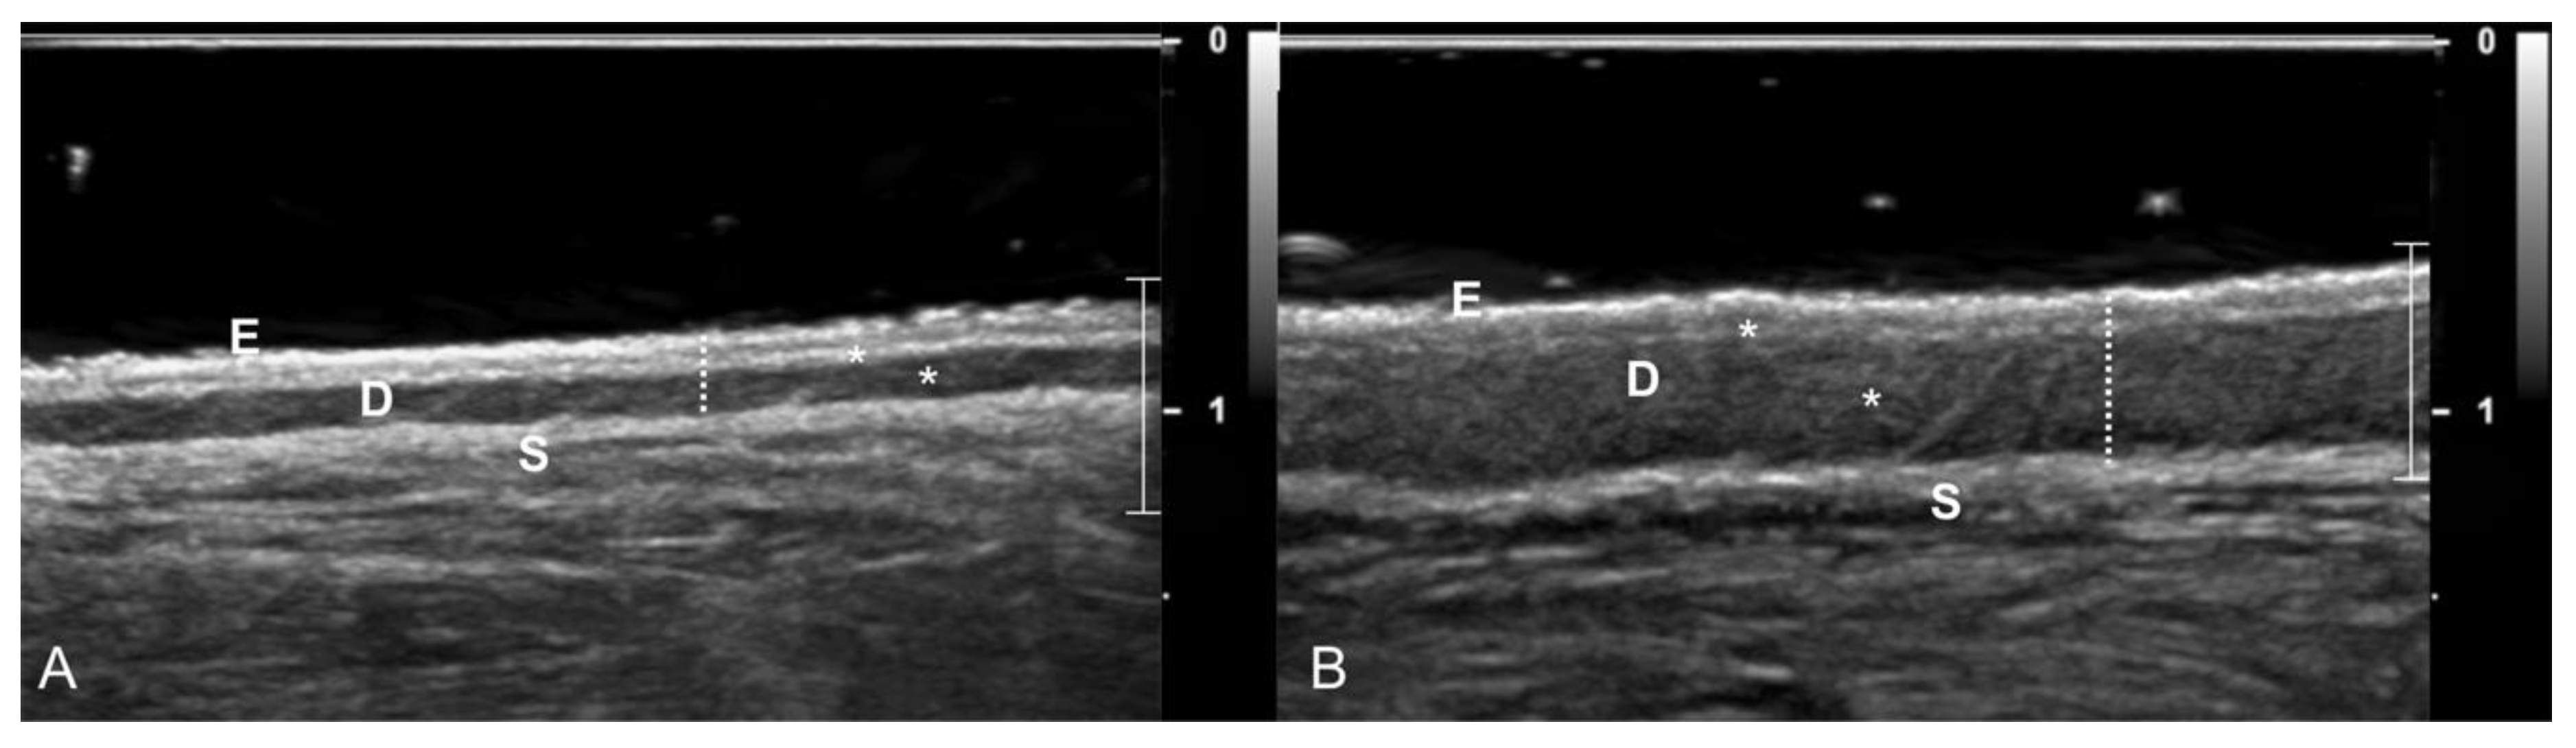

- Diana, A.; Preziosi, R.; Guglielmini, C.; Degliesposti, P.; Pietra, M.; Cipone, M. High-frequency ultrasonography of the skin of clinically normal dogs. Am. J. Vet. Res. 2004, 65, 1625–1630. [Google Scholar] [CrossRef]

- Diana, A.; Guglielmini, C.; Fracassi, F.; Pietra, M.; Balletti, E.; Cipone, M. Use of high-frequency ultrasonography for evaluation of skin thickness in relation to hydration status and fluid distribution at various cutaneous sites in dogs. Am. J. Vet. Res. 2008, 69, 1148–1152. [Google Scholar] [CrossRef] [PubMed]

- Zanna, G.; Fondevila, D.; Ferrer, L.; Espada, Y. Evaluation of ultrasonography for measurement of skin thickness in Shar-Peis. Am. J. Vet. Res. 2012, 73, 220–226. [Google Scholar] [CrossRef] [PubMed]

- Milner, S.M.; Memar, O.M.; Gherardini, G.; Bennett, J.C.; Phillips, L.G. The Histological Interpretation of High Frequency Cutaneous Ultrasound Imaging. Dermatol. Surg. 1997, 23, 43–45. [Google Scholar] [CrossRef]

- Szymańska, E.; Nowicki, A.; Mlosek, K.; Litniewski, J.; Lewandowski, M.; Secomski, W.; Tymkiewicz, R. Skin imaging with high frequency ultrasound—preliminary results. Eur. J. Ultrasound 2000, 12, 9–16. [Google Scholar] [CrossRef]

- Eisenbeiss, C.; Welzel, J.; Eichler, W.; Klotz, K. Influence of body water distribution on skin thickness: Measurements using high-frequency ultrasound. Br. J. Dermatol. 2001, 144, 947–951. [Google Scholar] [CrossRef]

- Mantis, P.; Tontis, D.; Church, D.; Lloyd, D.; Stevens, K.; Balomenos, D.; Gouletsou, P.G.; Gianoulopoulos, G.; Doukas, D.; Galatos, A.D.; et al. High-frequency ultrasound biomicroscopy of the normal canine haired skin. Vet. Dermatol. 2014, 25, 176-e45. [Google Scholar] [CrossRef] [PubMed]

- Heo, S.; Hwang, T.; Lee, H.C. Ultrasonographic evaluation of skin thickness in small breed dogs with hyperadrenocorticism. J. Vet. Sci. 2018, 19, 840–845. [Google Scholar] [CrossRef] [PubMed]